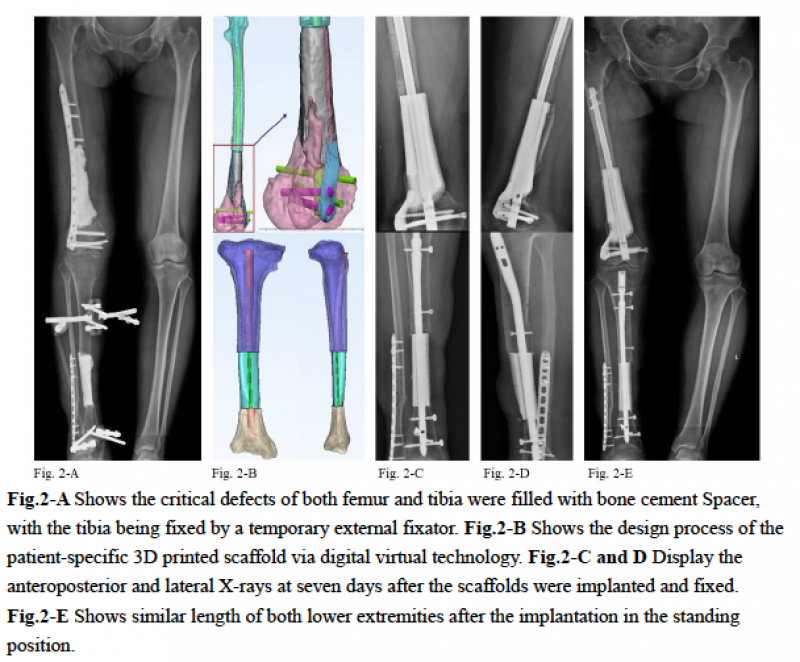

二期:8周后取出缺损区骨水泥Spacer,植入个性化设计的3D打印微孔钛合金假体,并分别进行股骨拟行髓内钉及胫骨髓内钉固定。

随访:术后复查X光片见右侧股骨、胫骨的对位、对线及下肢力线满意,骨缺损区匹配良好。术后26月仍见局部稳定,未见假体下沉及内固定松动,局部骨痂生长满意,同时患者膝、踝关节功能良好。

图2: 3D打印假体的设计及术后X光片